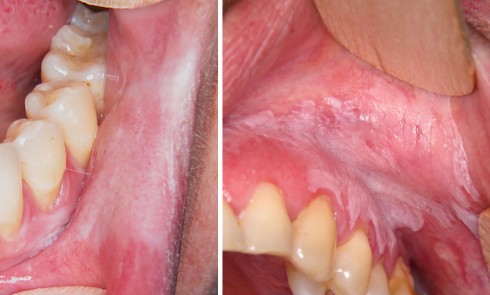

Article réservé à nos abonnés Un lichen peut en cacher un autre !

Cas 1 Motif de la consultation Patiente de 55 ans, qui a consulté pour une lésion blanche de la lèvre...